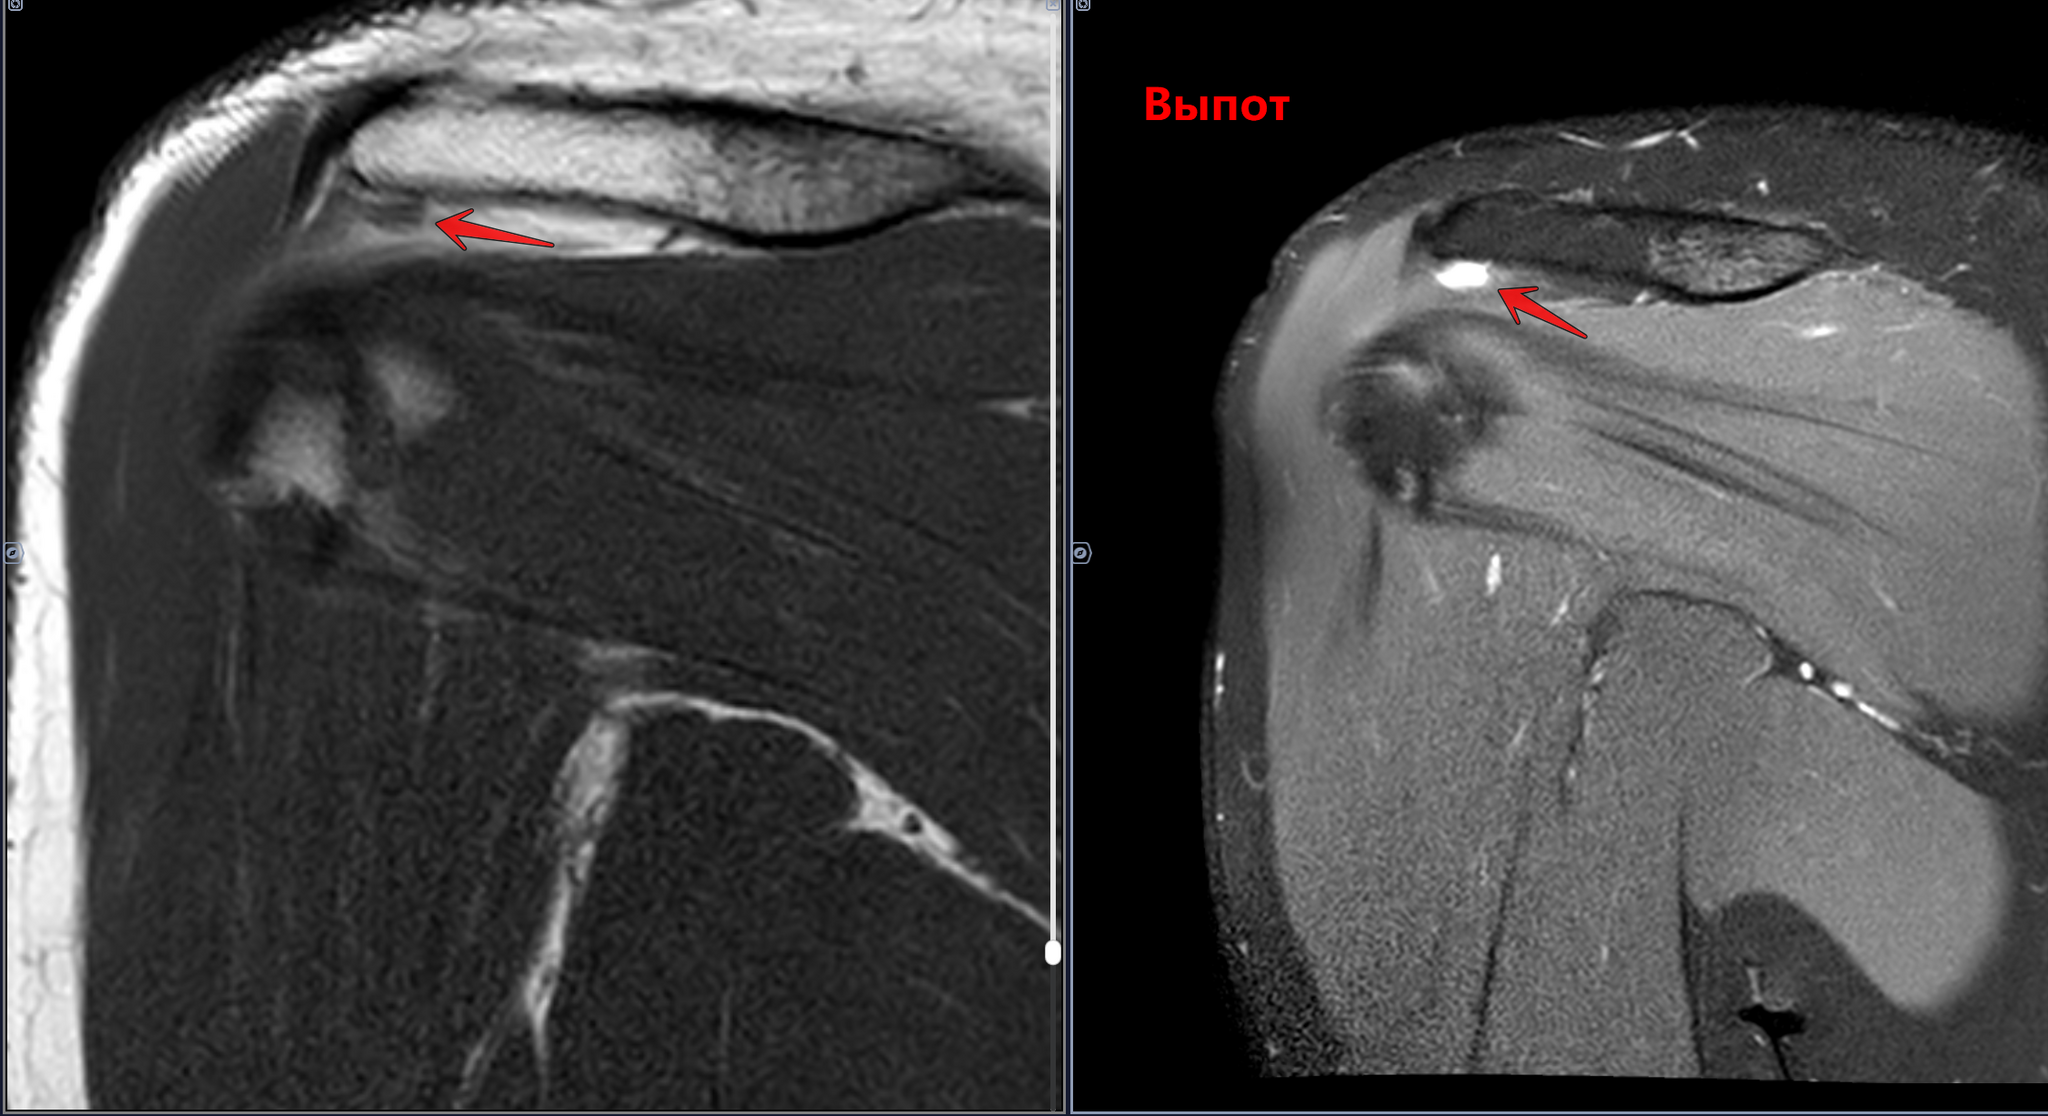

Сужение субакромиального пространства до 5.4мм(норма 7мм),отек суставной поверхности акромиона, в полости субакромиальной сумки- умеренное количество выпота. Заключение: Субакромиальный импиджмент, субакромиальный бурсит правого плечевого сустава.